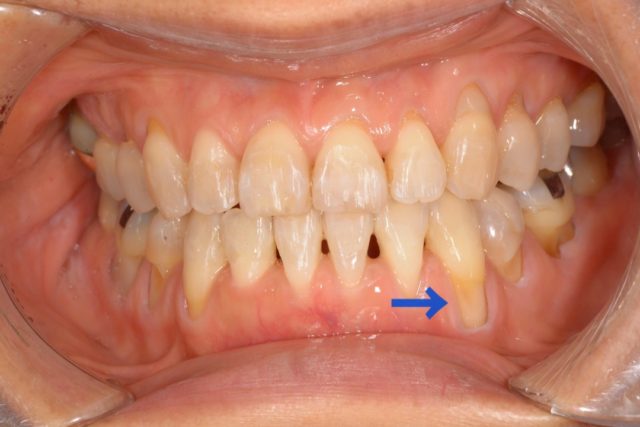

根面被覆術 No.2

根面被覆術について